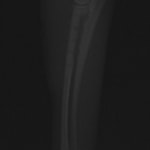

他院にて左大腿骨遠位の成長板骨折(salter-harrisⅠ型)が認められており、治療相談を目的として来院。当院にて、キルシュナーワイヤーを用いたピンニングにより骨折部位の整復を行いました。術後の経過は良好で、現在も経過観察中です。

術後レントゲン

Arthrex社のターゲティングデバイスを用いてピンニングの位置を調整することで、確実な固定を行っています。当院ではこの手術器具以外にも、人の手術にも使用される様々な器具を導入し、手術精度を高め、また医療メーカーと新しい器具の開発、試作にも取り組んでおります。